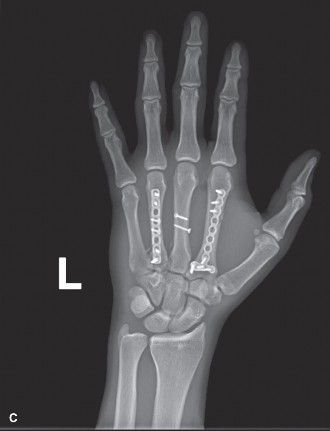

(Post-operative PA radiograph demonstrating anatomical reduction and stable internal fixation of the 2nd, 4th, and 5th metacarpal fractures with low-profile locking plates and screws.)

This transverse shaft fracture was reduced and fixed with a 1.5 mm low-profile locking plate with 5 holes, applying a compression technique to achieve interfragmentary compression. Two bicortical screws were placed proximally and two distally, avoiding the articular surfaces.

The short oblique, comminuted shaft fracture required careful reduction. A 1.5 mm low-profile locking plate (6 holes) was applied. Due to the comminution, the plate acted as a bridging plate, and locking screws were strategically placed. One lag screw was applied through the plate for interfragmentary compression of the oblique component, augmenting stability.

The highly unstable spiral and comminuted fracture posed the greatest challenge. After achieving anatomical reduction and confirming rotational alignment, a 1.5 mm low-profile locking plate (7 holes) was contoured and applied to the dorsal surface. Given the significant comminution and potential for bone void, the plate served primarily as a neutralization and bridging plate, with careful placement of locking screws to buttress the fragments. No primary lag screw was feasible given the comminution.